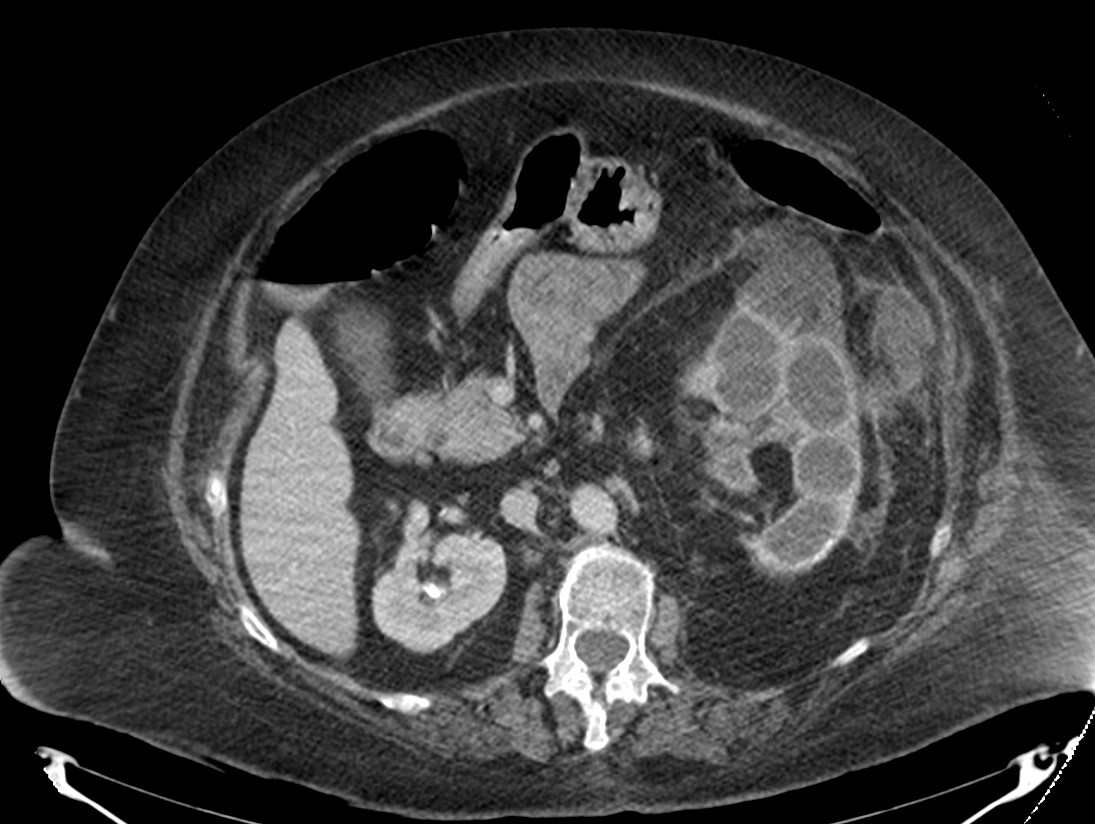

Tomografía Computarizada:

Es la técnica de elección por dos razones:

- Alta especificidad y definición de los hallazgos que permiten confirmar el diagnóstico.

- Descartar afectación extrerrenal y Planificación quirúrgica.

Estos hallazgos son altamente sujestivos de PNXG:

- Aumento difuso del tamaño y pérdida del contorno renal.

- Litiasis coraliforme: cálculo central en pelvis renal contraída (también puede existir calcificaciones intraparenquimatosas). La TC es la mejor técnica para identificar las litiasis.

- Riñón no funcionante (pobre o nula eliminación del medio de contraste en el riñón afectado).

- Cálices renales dilatados (áreas hipodensas) de apariencia multiloculada que se asemeja a una «pata de oso».

- También pueden darse abscesos o áreas de necrosis parenquimatosa.

- Cambios inflamatorios que excede los límites del riñón y genera colecciones periféricas o extensión hacia vísceras vecinas. Pueden darse abscesos en el psoas y fístulas (cutáneas o colónicas) que indican progresión de la enfermedad.

Aunque el área de hipoatenuación que se extiende desde la pelvis renal contraída hasta los cálices renales puede sugerir una hidronefrosis, la baja atenuación corresponde más bien a tejido inflamatorio antes que a líquido (la nefrostomía percutánea no siempre se lleva a cabo).

Veamos un caso.

Paciente mujer de 62 años que acude por decaimiento general con fiebre y dolor en flanco izquierdo. Ingresa en UVI por signos de sepsis

Nos cuenta antecedentes de pielonefritis e hidronefrosis crónica.

Hallazgos en imagen:

Estos hallazgos pueden ser dificiles de interpretar, ya que una paciente con hidronefrosis crónica y litiasis en el uréter puede haber sufrido una obstrucción que origina un cuadro de dolor en FRI con ruptura de cálices y colección extra axial. Otra probabilidad puede ser un angiomiolipoma que ha roto un aneurisma y ha producido un sangrado. También podríamos estar ante una pionefrosis aunque dada dada la clínica, los antecedentes y al observar los hallazgos en TC podríamos establecer la sospecha de pielonefritis xantunogranulomatosa con alta probabilidad. La confrimación vendrá dada con la nefrostomía y estudio de anatomía patológica.